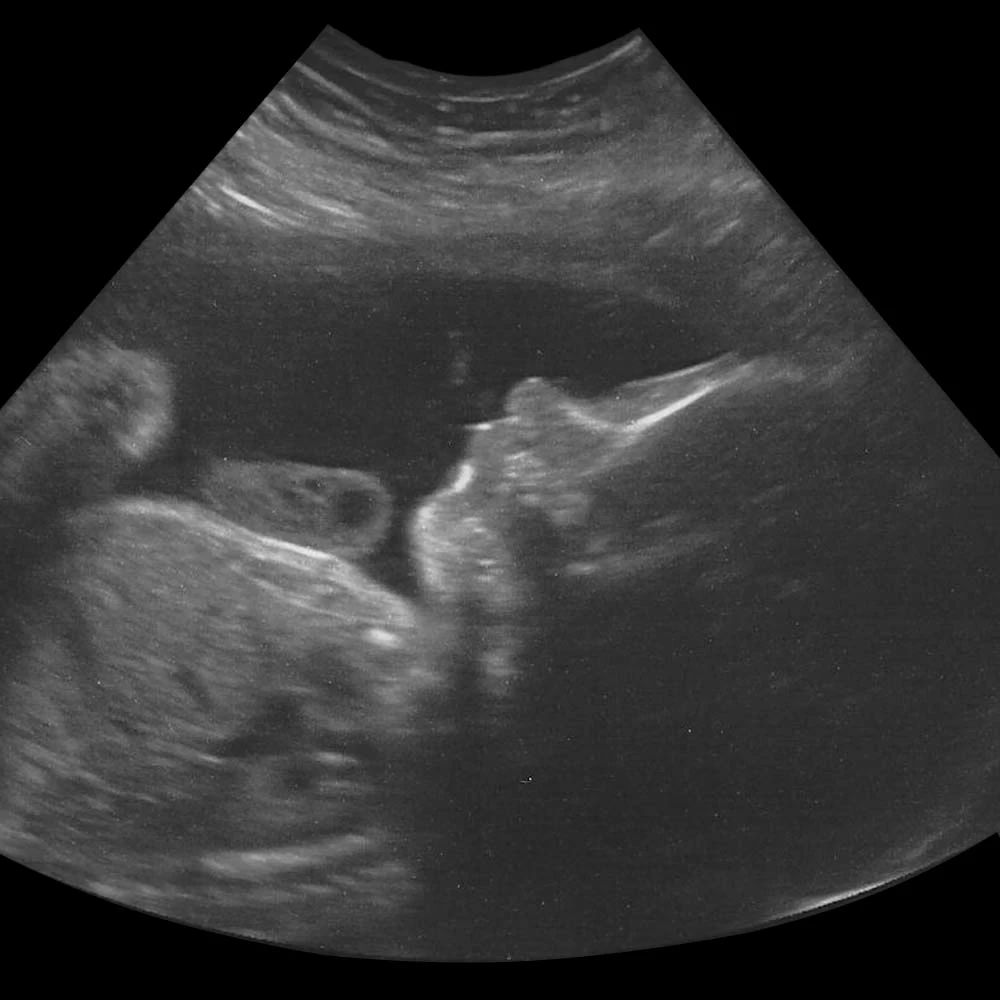

На четырнадцатой неделе при хорошем чувствительном аппарате УЗИ уже можно определить пол ребенка.